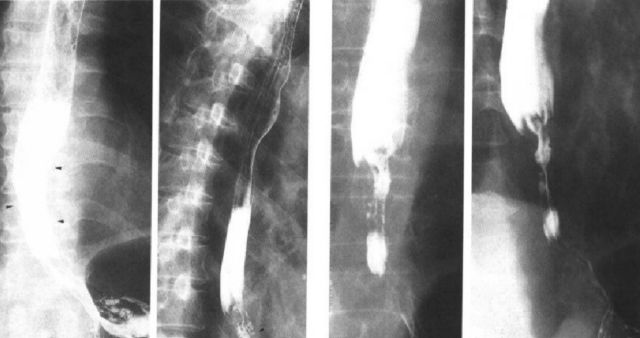

食管癌

因为食管癌的造影很复杂,所以不能用一句话简单概括。下面按照食管癌的早期和中晚期分别总结。

早期:局限 小(局限性黏膜皱襞紊乱和断、局限性管壁僵直;小充盈缺损、小龛影。)

中晚期:无“局限 小”(中晚期食管癌是整个食管的改变,不再是局限性改变。管壁僵直;充盈缺损、龛影;管壁狭窄。)

早期中下段食管癌

食管中下段黏膜皱襞局限增粗,中断,箭头所示,管壁僵硬。

早期食管癌

中晚期食管癌图像: